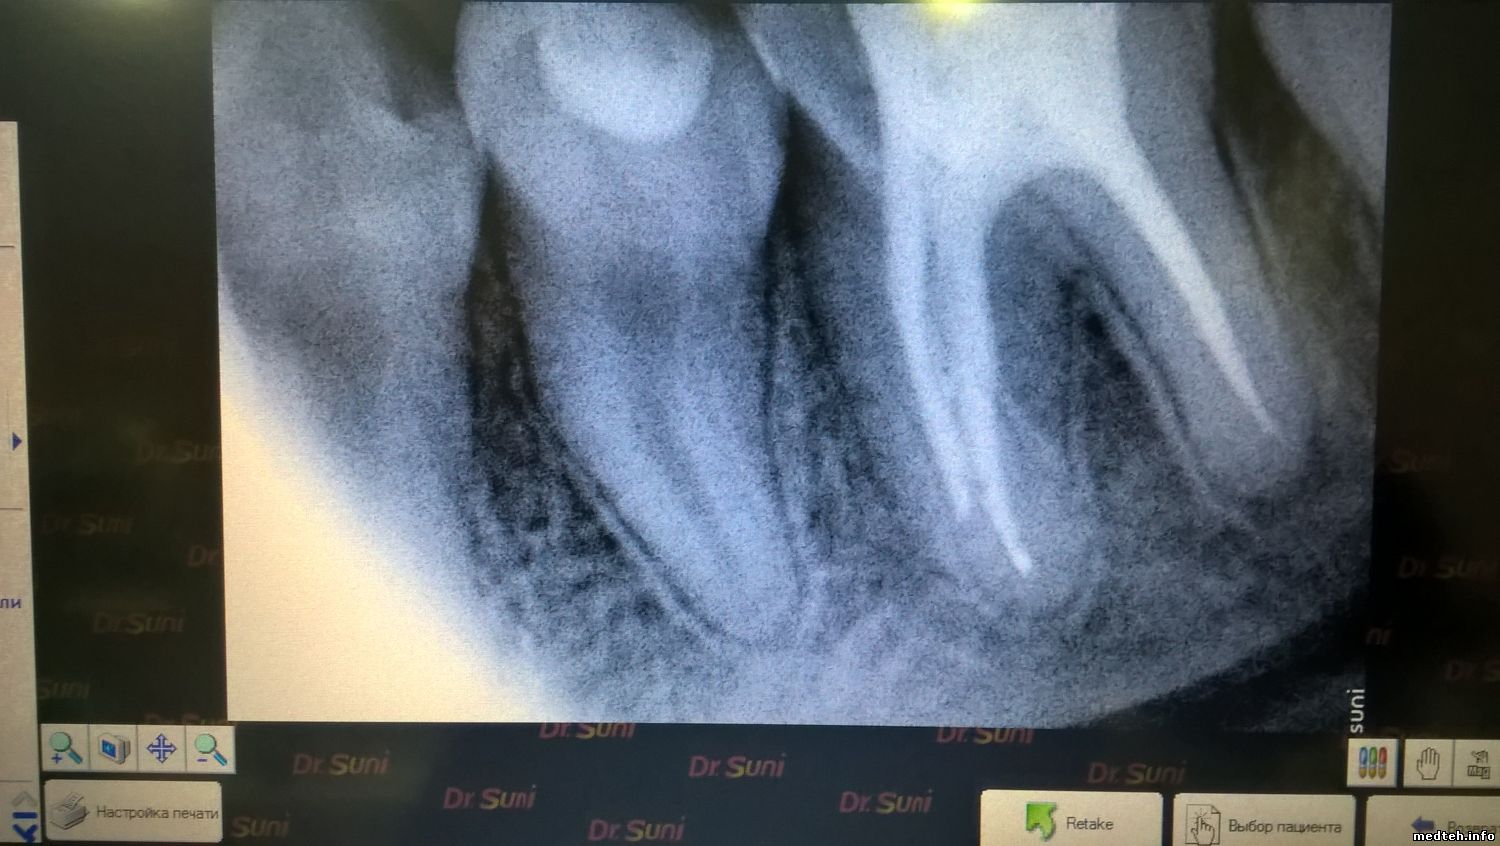

ломать провод это издевательство.. я сделал так в режиме ожидания крутил вертел провод (правда не так жестока) и в том числе местах соединения к датчику и блоку и даже шатал сам штеккер все окей... потом взял тупо отсоединил датчик и вот на тебе самопроизвольный снимок со снегом 5ый. получается дохнет датчик но странно как то дохнет получается почти 2 года от случая к случаю.. так на всякий случай фото датчика ( думаю фото само за себя говорит как относятся к датчику) и самопроизвольный снимок . drinks

да обратите внимание на 4ый снимок зубов сделан сегодня как на рекламных проспектах ничто не предвещает скорую смерть.

9982299.jpg (153.5 Kb) · 0289984.jpg (207.6 Kb) · 8127800.jpg (70.9 Kb) · 1014884.jpg (163.0 Kb) · 4819625.jpg (124.7 Kb)